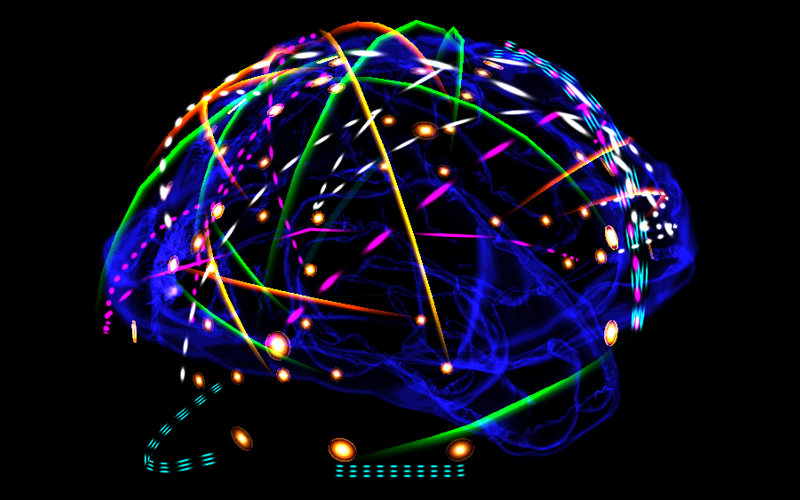

MEG data visualization and navigation tool: Synchronization biomarkers of MCI patients [Antonio Gracia, UPM]